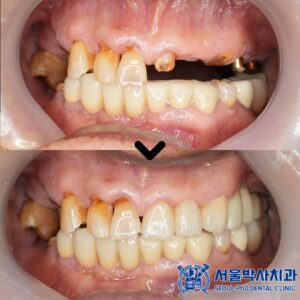

위 환자분은 앞니가 많이 불편해서

임플란트 치료를 고민하고 계셨는데요.

치아를 확인해보니 앞니 두 개는

치아의 뿌리 부분만 남아 있었고,

심한 치주염과 충치로 인해

유지하기 어려운 상태였습니다.

치료 마무리 후 사진입니다.

환자분께서도 최종 보철물을 장착한 후

너무 자연스럽고 불편한 곳도 없다며

매우 만족스러워 하셨습니다.